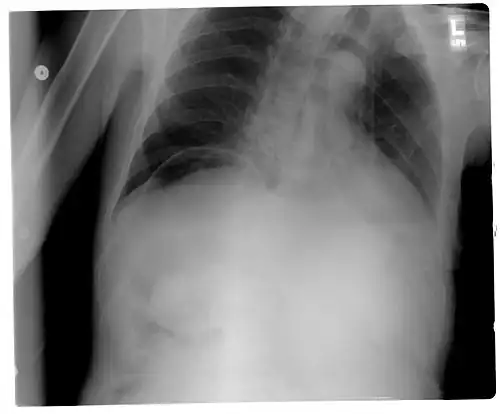

Signs that can be seen on projectional radiography are shown below:

-

Another pneumoperitoneum on chest X-ray. -